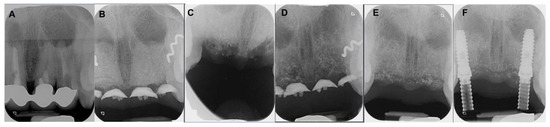

4.1. Patient No. 1

4.2. Patient No. 2

4.3. Patient No. 3

4.4. Patient No.4

4.5. Patient No.5

4.6. Patient No.6

| Patient Gender Age | Medical History of Interest [Toxic Habits] Type of Surgery | Closure by First Intention [Collagen Sponge] | I.M. | I. C. | Healing | Early Postoperative Complications | Late Postoperative Complications |

|---|---|---|---|---|---|---|---|

| 1 F 63 | NO [Tobacco: 2 cig/day] Horizontal Guided Bone Regeneration | Yes [No] | G | No | G | No | No |

| 2 M 52 | NO [-] Alveolar ridge preservation | No [Yes] | G | No | M | Graft loss and self-limited alveolitis | No |

| 3 M 61 | NO [-] Alveolar ridge preservation | Yes [No] | G | No | G | No | No osseointegration of the implant, replacement in 3 months, without problems and with good stability |

| 4 F 46 | NO [-] Alveolar ridge preservation | No [Yes] | G | No | M | Graft loss and self-limited alveolitis | No |

| 5 M 64 | NO [-] Sinus lift with lateral window | Yes [No] | G | No | G | No | No |

| 6 M 46 | NO [-] Sinus lift with lateral window | Yes [No] | G | No | G | No | No |